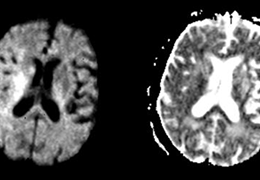

Task fMRI

Single-input Processing.

Avoid delays through an automated pre-processing pipeline. Generate activation maps within seconds.

Combine structural and functional information by utilizing activations in tractography.

Rest fMRI

Complete set of clinically significant networks.

Select and review multiple clinically significant networks, computed through a fully automated pipeline.

Correlate task and rest fMRI results in a unified interface.